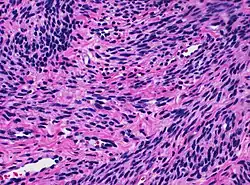

![]() Histology of myometrium | |